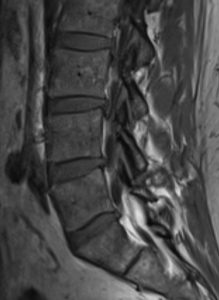

February 17: Got an MRI of my lower back after complaining to the Ortho PA that nothing was being done for my back pain given that my foot had been numb for over a month after my back injury in January. I had forced the issue by offering to pay for the MRI since insurance was resistant to do so since I had not done any PT.

February 26:  The Ortho PA was on vacation for a week so I finally got my MRI results which indeed showed a ruptured disc between L5 and S1 in my lower back so she started me on a 7-day course of Prednisone.  My blood pressure (which I track daily) went from a nominal 122/80 to 140/91 and stayed elevated for the days I was on Prednisone. The Ortho PA told me again to go to PT which I, again, did not.